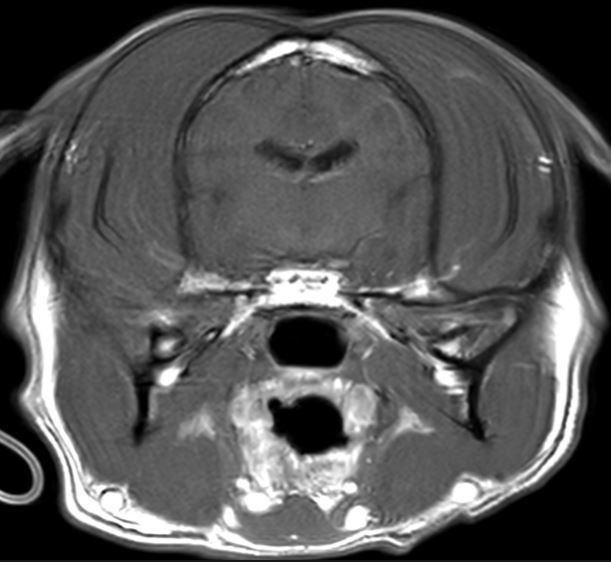

Q

What artifact is this?

Motion/Phase mismapping

A